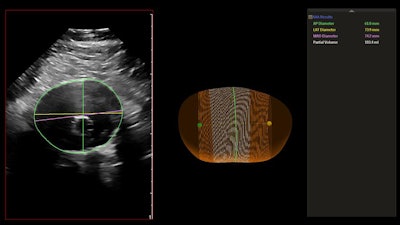

The AAA model provides measurements including the maximum anterior-to-posterior diameter and partial volume of the aneurysm, while also indicating the centerline. Image courtesy of Philips Healthcare.